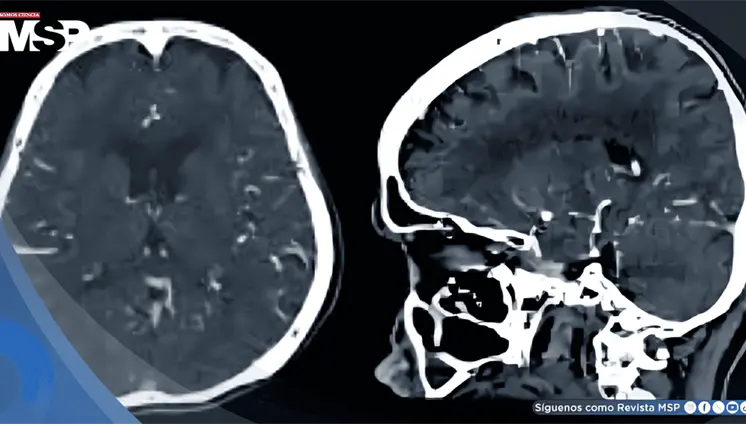

La enfermedad avanzó de forma silenciosa durante años, manifestándose únicamente con cambios de personalidad, deterioro cognitivo e incontinencia, lo que llevó a un diagnóstico tardío.